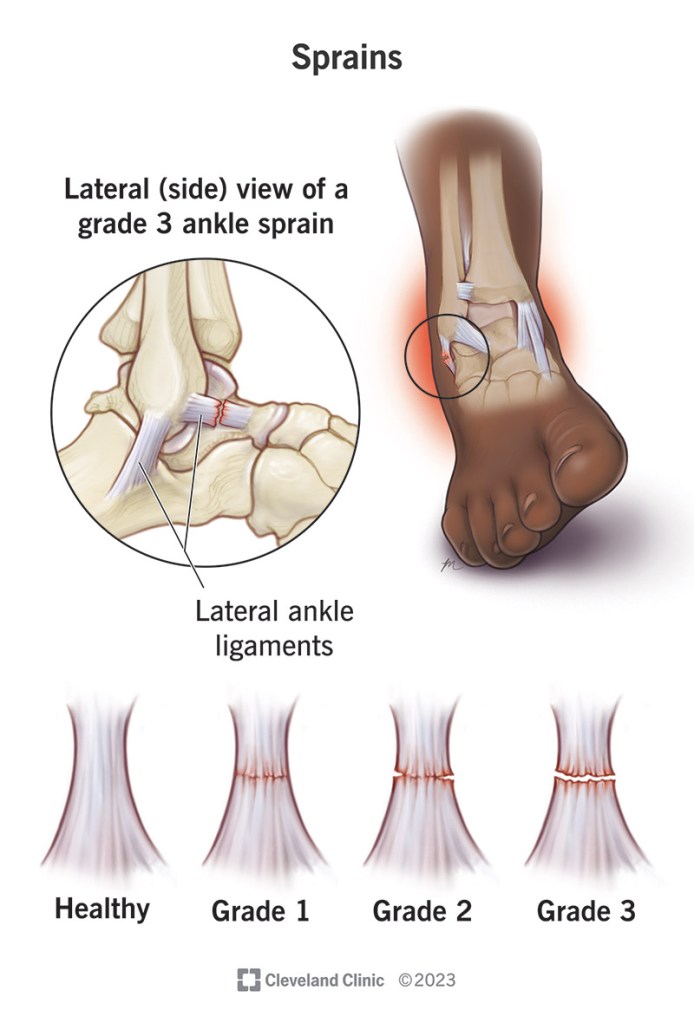

Answer: C) Grade 2

Explanation: Grade 2 sprain is a partial tear. On MRI a high signal with partial ligament disruption is seen

A) is incorrect as this is not a valid grade.

B) is incorrect because grade 1 is mild stretch with intact fibres.

D) is incorrect because grade 3 is a complete rupture with no continuity.

E) is incorrect because grade 4 is not part of standard classification.